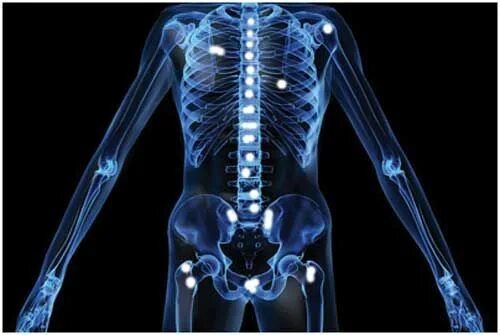

Метастазы по всему скелету